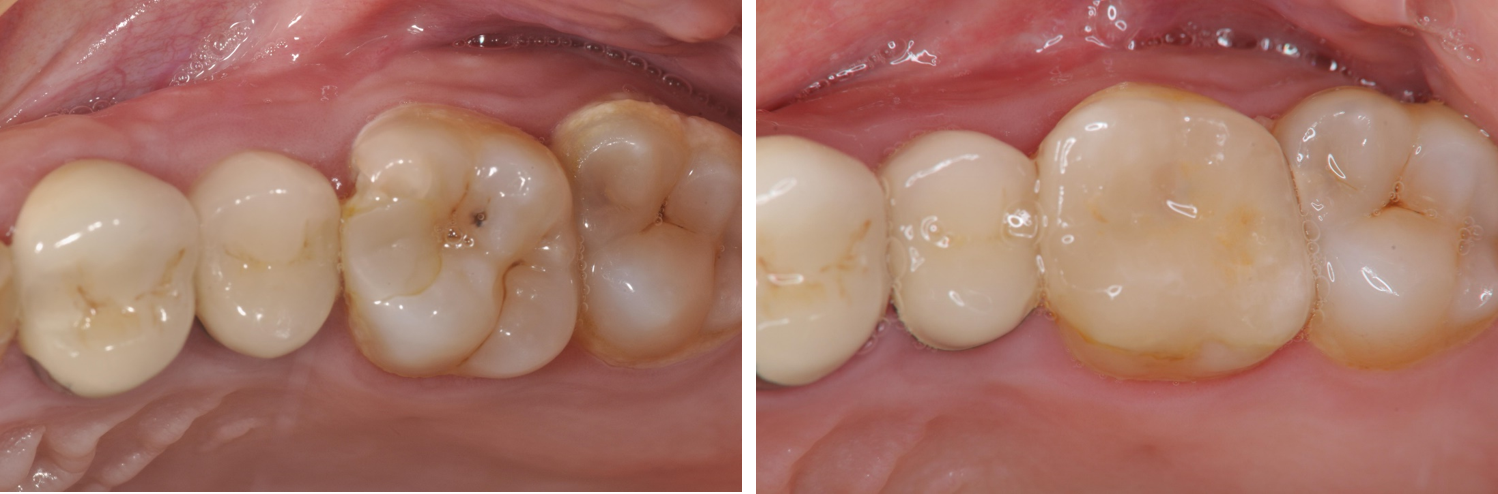

術前、術後比較

治療前,嚴重二次蛀牙

治療後口內照